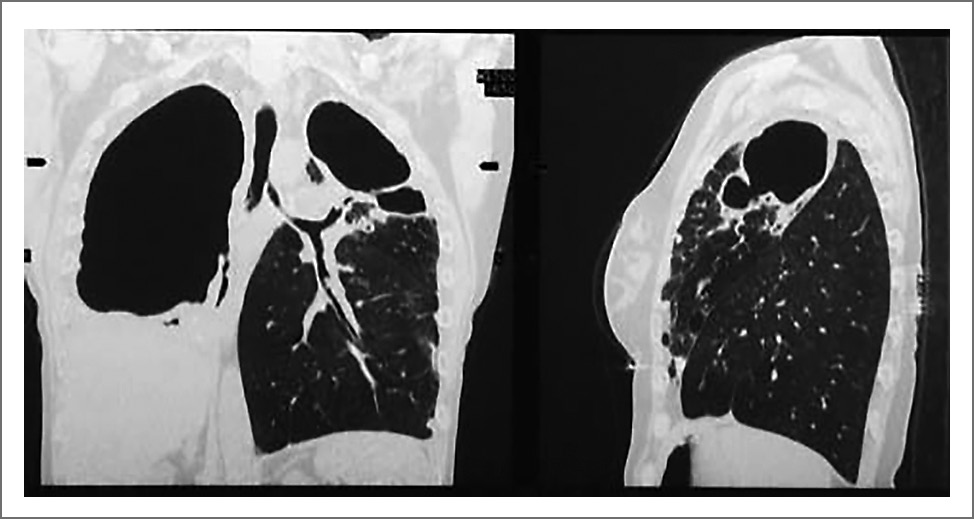

– Я понимаю, о чем Вы говорите. Но я могу доказать свою точку зрения. Приведу небольшую статистику лечения лекарственно-устойчивого туберкулеза легких на нашей базе НИИФП ФГАОУ ВО «Первый МГМУ им. И.М. Сеченова» (Сеченовский Университет) с 2011 по 2017 г. В основном это пациенты с разным типом лекарственной устойчивости (табл. 1). Почти у 70% всех больных – ФКТ (рис. 3), у 25% – туберкулема (рис. 4). Особую опасность представляет казеозная пневмония, так как без оперативного вмешательства смертность может достигать 99% (рис. 5).

Рис. 3. ФКТ: а – на КТ органов грудной клетки; b – на макропрепарате.

– Наиболее тяжелую клиническую ситуацию я описал в 2017 г. в журнале «Interactive Cardiovascular» [4]. Ко мне попала пациентка 46 лет, которая страдала туберкулезом легких в течение 13 лет. Несмотря на многочисленные курсы химиотерапии, сформировался ФКТ с тотальной деструкцией правого легкого и верхней доли левого легкого (рис. 7). Состояние осложнялось развившейся тотальной эмпиемой плевры с бронхоплевральным свищом. На основании посева мокроты у женщины определили ШЛУ-ТБ, а посев жидкости плевральной полости показал наличие Pseudomonas aeruginosa. Также у пациентки заболевание осложнилось амилоидозом почек, кахексией и дыхательной недостаточностью. Жизненная емкость легких при поступлении – 41% от долж., объем форсированного выдоха за 1-ю секунду – 25% от долж. Тест с 6-минутной ходьбой составил 270 м.

Рис. 7. КТ органов грудной клетки пациентки перед операцией. Определяется ФКТ с тотальной деструкцией правого легкого и верхней доли левого легкого.